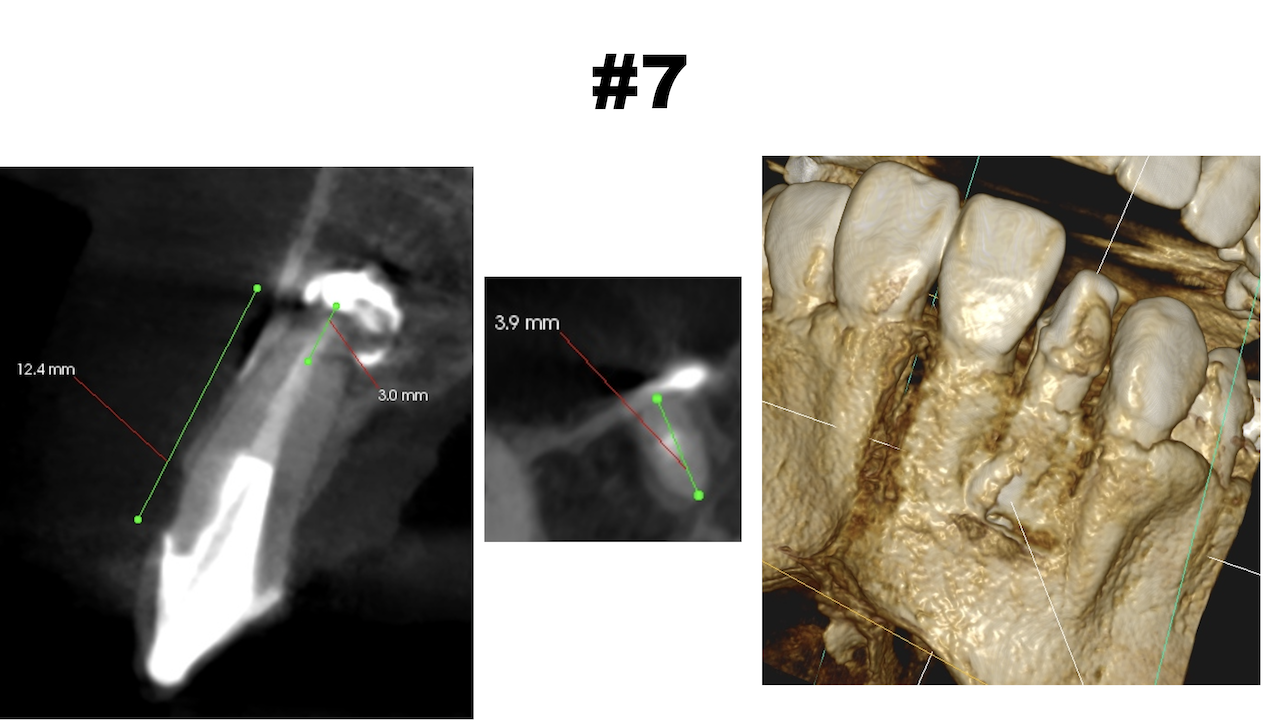

CBCT(2025.10.21)

Apexよりも12.5mm下方に#7のApexがあり、そこを3mm切断しようとすれば頬舌的に3.9mの切断が必要だ。

Apexの位置はクラウンマージン部より12.5mm下方だ。